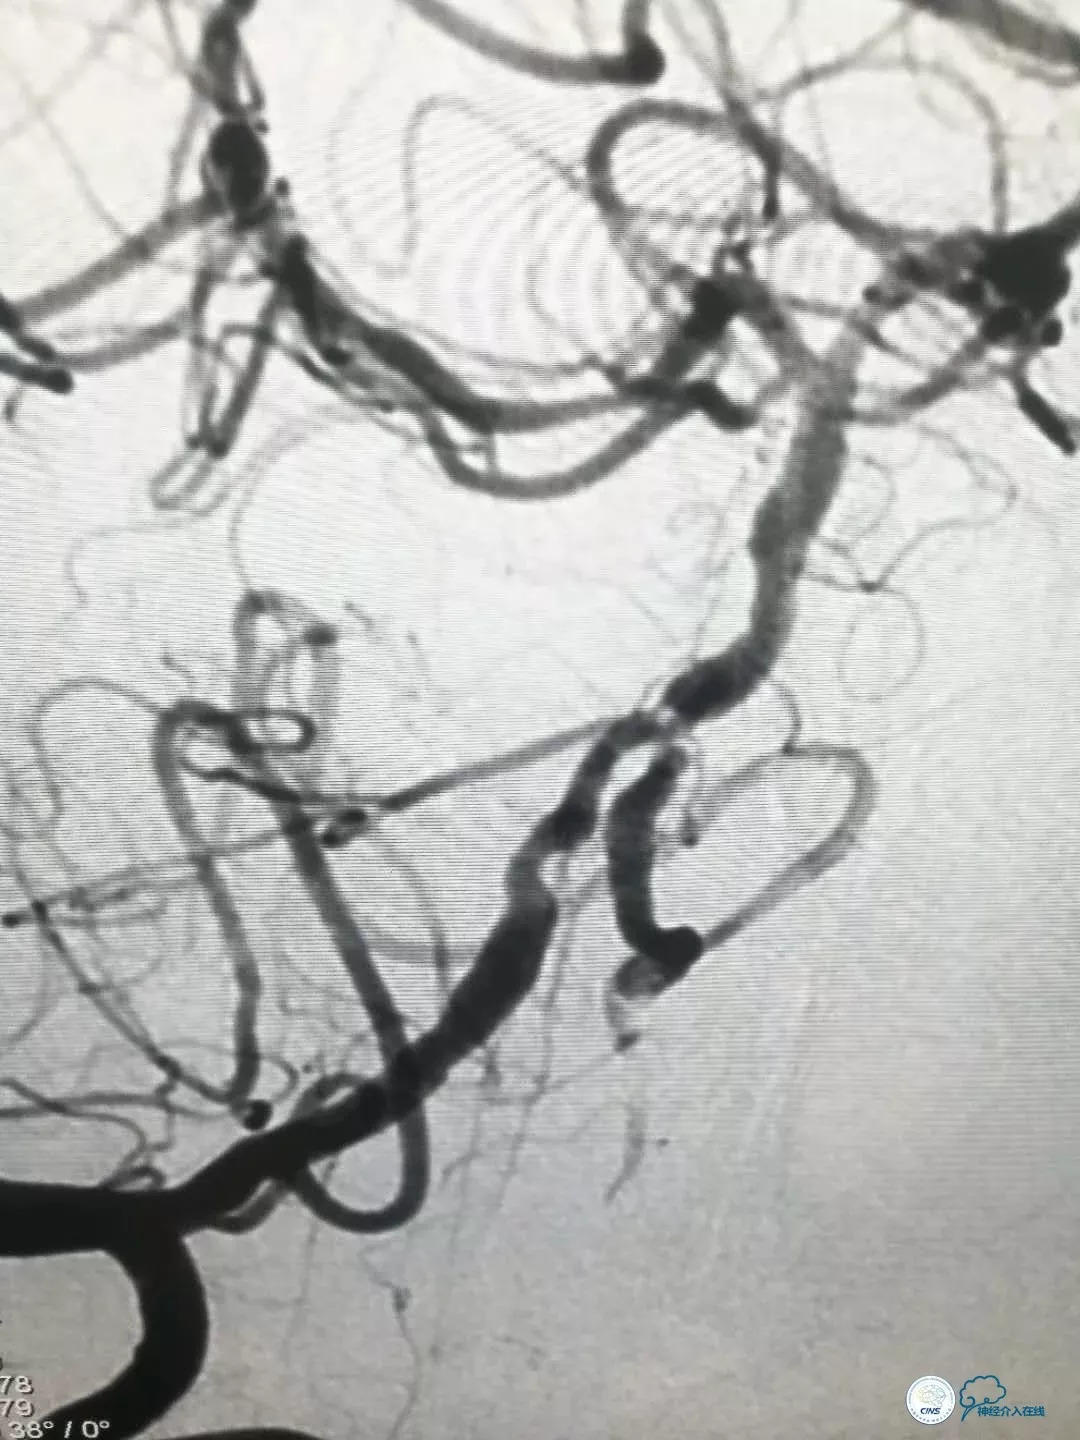

DSA提示: 右椎动脉V4段及基底动脉近端串联重度狭窄,左椎动脉开口迂曲,左椎动脉V4段重度狭窄,发出PICA后以远显影浅淡,左颈内动脉后交通段动脉瘤(2×2.5mm)(图4-8)。

图4

全麻下右股动脉入路, 6F导引导管至右椎动脉V2段远端,术前造影示右侧椎动脉及基底动脉重度狭窄,局部可见充盈缺损,考虑斑块掀起(图9)。

图9